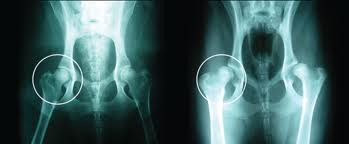

Displasia de caderas o codoLa displasia de cadera es una enfermedad de tipo hereditario, poligonica y multifactorial. Se inicia en los primeros meses de vida apareciendo una laxitud de la articulacion coxofemoral. Como consecuencia de ello y durante el periodo de crecimiento se desarrolla una mala articulacion que progresa hasta aparecer signos de osteoartritis y subluxacion de la articulacion.El animal afectado puede manifestar síntomas muy diversos, que básicamente se resumen en problemas más o menos acentuados de desplazamiento del tren trasero (corre como un conejo, se sienta de modo extraño, rehusa subir escaleras, a veces cojea de alguna pata trasera, mueve las caderas de modo extraño....). No existe concordancia entre el grado de afectación de la cadera y los síntomas del animal (perros muy afectados apenas dan una leve cojera, y otros con un grado bajo de displasia pueden llegar a arrastrarse, y viceversa).El tratamiento depende del grado de displasia, la edad del animal y la parte de la cadera que presente degeneración, así como el nivel de ésta (es positivo un diagnóstico precoz). Algunas mejoran sustancialmente con tratamiento conservador (condroprotectores, restricción del ejercicio, que el perro se mantenga delgado...), pero la mayoría necesitan cirugíaEl diagnostico se realiza mediante radiografias bajo anestesia y que oficialmente A.V.E.P.A certifica.Hoy por hoy no estan Tipificados los perros que transmiten esta enfermedad, por lo que es dificil su diagnastico cuando el perro es muy joven ( entre 4-5 meses de edad). Solo existen pruebas de diagnastico orientativo que son dinamicas y no realizan habitualmente (porcentaje de probabilidad).Esta establecido cientificamente que perros fenotipicamente libres de displasia pueden transmitir las enfermedades a las futuras camadas en un 20-25%.Esta displasia ocurre en un gran porcentaje cuando los componentes del arbol genealogico del cachorro no estan controlados y aptos para la cria.2. DISPLASIA ADQUIRIDALa displasia de cadera adquirida puede ser debida a un ejercicio prematuro del animal el cual puede producir los siguientes problemas:Exceso de musculacion que producira una constante presion sobre el eje del femur con respecto al encaje del mismo (acetabulo).Desgaste de los cartalagos todavia no formados.Crecimiento demasiado prematuro debido a una alimentacion inadecuada.Sobrepeso debido tambien a una mala alimentacion o a una sobredosis diaria de alimento.Suplementos de calcio sin prescripcion Veterinaria o alimentacion a base de carne y desequilibrada.3. COMO DESPISTARLAAdquirir su cachorro en un criadero especializado en la raza y solicitar informacion al criador sobre los certificados de '' Libre de Displasia'', ademos, que no se dedique a la cria o venta de cachorros de todas las razas o de muchas de ellas.Ver los padres y exigir comprobar su identificacion (MICROCHIP) quedandose a posteriori con las fotocopias de los mismos.Ver los originales de los certificados oficiales conforme los padres estan aptos para la cria. Para que estan aptos para la cria, los resultados no deben de exceder de la letra "C" para los examenes que se hayan realizado en "A.V.E.P.A" (Asociacion de Veterinarios Españoles de pequeños animales) o de la cifra total de 30 en los certificados oficiales emitidos por el "B.V.A." (British Veterinarian Asociacion). Los certificados no son validos si no han sido emitidos por un organismo oficial y solo hay uno por pais. Cualquier certificado oficial emitido por un veterinario sin reunir lo (anteriormente) dicho no es valido.IMPORTANTES PREGUNTAS Y SUS RESPUESTASPregunta:¿ Si el Padre y la Madre estan libres de displasia, los Hijos entonces no pueden nunca heredar displasia ni tampoco taras oculares ?Respuesta: No es asi. Si los Padres estan controlados el riesgo disminuye y mas aun si los Abuelos y Tatarabuelos tambien lo estan o estaban pero siempre puede haber un riesgo ya que hoy por hoy no estan tipificados los perros que transmiten esta enfermedad. Lo que si es seguro es que si los Padres no estan controlados, el riesgo es muy alto.Pregunta: Si el perro geneticamente tiene que ser displasico se puede evitar que la padezca con unos cuidados especificos?Respuesta: No. Si el perro lleva geneticamente la displasia, esta se desarrollara sin duda por mas que quisieramos prevenirla, pero si no la lleva y no se le cuida en su crecimiento entonces es obvio que tambien la puede adquirir de forma no genetica.Nota: Actualmente en España no son demasiados los ejemplares reproductores que sean poseedores de estos certificados, Sin embargo algunos criadores nos vamos concienciando y realizamos las radiografias a nuestros ejemplares reproductores, el motivo por el que no todos los perros tienen este certificado es, que la R.S.C.E, no obliga a los criadores a obtener los mismos para poder realizar camadas. CondrodisplasiaSe trata de una enfermedad genética y hereditaria que afecta al perro a nivel óseo: provoca un acortamiento de los huesos largos (patas) y un engrosamiento de las epífisis, con desviación lateral de las manos. En climas calurosos, su salud corre peligro: se fatiga en exceso y su piel suele cubrirse de eczemas una situación peligrosa para su salud. Taras ocularesl igual que en humanos, consiste en un aumento de la presion intraocular, que produce un deterioro de las estructuras internas. En muchos casos puede llegar a provocar la ceguera total del ojo afectado. El aumento de la presion se produce como consecuencia de un drenaje insuficiente del humor acuoso del ojo, generalmente porque existe una alteracion anatomica del angulo iridocorneal (angulo de drenaje) o porque existe un obstaculo que impide ese drenaje.posibles taras:glaucoma ocularay dos tipos de glaucoma:Glaucoma primario: de origen hederitario. Se manifiesta alrededor de los 2 o 3 años de edad, y normalmente comienza afectando a un solo ojo, para meses mas tarde aparecer en el otro.Glaucoma secundario: causado por otros factores no geneticos, por ejemplo, por una herida penetrante en el ojo. Esto a su vez causa una inflamacion y el humor acuoso del ojo se vuelve denso y es incapaz de drenar normalmente. Tambien puede estar provocado por tumores, infecciones, etc.Detectarlo es de extrema importancia pues, cuanto mas tiempo pase, mas riesgo habra de perder la vision del ojo afectado. Los signos que debemos observar seran dolor en el ojo (el perro se frota con su pata o contra otras superficies), pupila dilatada, cornea opaca y mirada enrojecida (los vasos sanguineos de la parte blanca del ojo estan dilatados). Normalmente si esto ultimo ya se ha manifestado, la vision del ojo esta perdida. El tratamiento de esta enfermedad se hace quiurgicamente, ya que los medicamentos existentes (de medicina humana), no llegan a solucionar completamente el problema. El glaucoma secundario se soluciona una vez que se ha eliminado la causa que lo produjo. cataratas juvenilesLas cataratas hereditarias o juveniles se manifiestan por una opacidad en el cristalino del perro joven a partir de los 3 meses de edad. Estas cataratas son diferentes de las cataratas no hereditarias que afectan a los perros adultos mayores o viejos. La función del cristalino del ojo es de enfocar los rayos de luz para que formen una imagen en la retina. Una opacidad o catarata del cristalino causa que entre menos luz en el ojo y la visión pueda verse disminuida.La catarata puede causar desde una leve disminución en la visión hasta la ceguera total en casos graves. Las cataratas también pueden clasificarse de acuerdo a su localización y estado de desarrollo. La catarata congénita másfrecuente en el Siberian Husky aparece en la región posterior del cristalino. No es raro que una catarata se desarrolle primero en un ojo, meses antes de que el otro ojo muestre los efectos de la enfermedad. La investigaciones recientes en ADN indican que las cataratas juveniles pueden ser transmitidas por un gen recesivo el gen esta ligado al sexo, en concreto, al cromosoma X, por lo que hay mas proporcion de machos afectados que de hembras. Hemeralopia (ceguera diurna)Como su apodo sugiere, la hemeralopia afecta a la vision del perro bajo luz brillante. Por la noche o en el interior de un local poco iluminado, la vision del perro es perfectamente normal. Es una enfermedad hederitaria, simple autosomal recesiva, lo que indica que ambos padres deben ser portadores (aunque tengan vision normal) para transmitirla a los cachorros. La enfermedad consiste en una degeneracion de los conos (celulas encargadas de la vision diurna y de la percepcion del color).Puede detectarse en cachorros de 7 semanas de edad, cuando el criador observa que, con luz diurna, chocan con objetos y parecen inseguros en las distancias. En caso de duda, se puede aplicar una tecnica llamada electroretinografia (ERG). distrofia cornealLa distrofia corneal afecta a la córnea o a la parte transparente externa del globo ocular. En la mayoría de los casos, los Siberianos con este desorden tendrán una acumulación de lípidos anormal en la córnea clara del ojo que resultará en una opacidad de córnea.Los oftalmólogos clasifican a la localización de la opacidad como "stromal" anterior, medio, o profundo. El Siberian Husky es propenso a la distrofia stromal profunda que está compuesto por depósitos de triglicéridos. La distrofia anular también ocurre y se observa como una opacidad en forma de anillo grueso (N. del T.: forma de "doughnut") en el área periférica de la córnea. La distrofia corneal se ve normalmente en adultos jóvenes y puede afectar a hembras más que a machos. La visión raramente es afectada yactualmente no existe terapia eficaz para tratar este defecto. Los recientes tests sugieren que un gen recesivo de expresión variabletransmite este desorden. atrofia progresiva de la retina La PRA afecta la retina, el revestimiento interno sensible a la luz (fotosensible) de la parte posterior del globo ocular. La retina contienedos tipos de células especializadas, los conos y bastones. Los bastones son necesarios para la visión en la penumbra o nocturna, y los conos se usan para la luz de día. El Siberian Husky tiene un tipo único de PRA que sólo se encuentran en el Siberian Husky y en el hombre.Este tipo de PRA se llama XLPRA (PRA ligado al gen X) ya que se transmite a través del cromosoma XX de la hembra. Causa una pérdida de visión nocturna seguida por pérdida de visión diurna, y eventualmente ceguera. El gen recesivo para el XLPRA está situado en el cromosoma X de la hembra. Las hembras que hereden un gen defectuoso en el cromosma X de un padre y un gennormal en el otro cromosoma X del otro padre, no serán seriamente afectadas.Ellas serán portadoras con fallas retineanas muy sutiles y ninguna pérdida de visión. El cachorro macho de una hembra portadora recibirá : o un gen defectuoso o un gen normal, dependiendo de cual cromosoma fue copiado en la replicación de DNA. Si él tiene el gen defectuoso, el perro estará afectado con PRA ya que los machos tienen un cromosoma XY. La enfermedad en machos puede ser devastadora con pérdida de visión hasta en cachorros a partir de los 5 meses de edad.Se está desarrollando un test genético para identificar a las hembras portadoras en el Siberian Husky. Una vez que este test esté disponible, el XLPRA podrá ser eliminado de los programas de cría. Un veterinario especialista debe hacer examenes oftalmologicos a los reproductores de estas tres afecciones (glaucoma, distrofia corneal y atrofia progresiva de retina) cada 2 años al menosDistrofia del folículo pilosoEs un proceso que afecta a la calidad del manto del animal. Aun está en estudio su transmisión y mecanismo, aunque se sabe que hay un claro componente hereditario. En el alaskan malamute hay una enfermedad similar (coat funk). Los animales afectados empiezan a perder el pelo de guarda (el más largo y duro, lo que se pierde en las mudas es la lana o subpelo), presentando el que conservan un aspecto quebradizo y seco, a menudo de coloración extraña (rojiza, color paja...). El subpelo queda expuesto, dando al perro un aspecto "de cachorro". Suele empeorar claramente en verano, para mejorar durante la estación fría. Generalmente acaba por afectar a todo el cuerpo, a excepción de la cabeza. La calidad del vida de nuestra mascota no se ve seriamente afectada, pero sí su resistencia al frío y climas extremos (calor incluido), por lo que no deberían utilizarse los animales afectados para la reproducción, ya que, no lo olvidemos, el siberian husky es un perro de tiro de clima ártico (y con un defecto grave en su manto, ya no puede cumplir la mitad de su cometido). Hasta ahora no se conoce cura, se observa una cierta mejoría con la castración (para luego reaparecer igual que antes), de modo que lo mejor es prevenir mediante la selección cuidadosa de reproductores. Dermatosis por carencia de zincOtra enfermedad de carácter leve que afecta a los perros nórdicos. Es un defecto en la absorción intestinal de zinc, aun cuando éste aparezca en la dieta en cantidades suficientes. El zinc se encarga del mantenimiento de las estructuras cutáneas. En su ausencia, el perro presenta un problema de picor (más o menos intenso) con pérdida localizada de pelo, en las uniones mucocutáneas (ojos, orejas, labios...), codos y testículos. Su aparición, en animales jóvenes, suele asociarse a situaciones de estrés, para luego volver al estado normal. No suele ser grave, pero resulta molesta para perro y dueño. El tratamiento pasa por suplementar la dieta con importantes cantidades de zinc durante un tiempo, a veces de por vida, o bien ayudar a la resolución de las lesiones mediante suplementos de ácidos grasos (las heridas creadas por el rascado tardan en cicatrizar debido a la falta de zinc, con este suplemento mejoran sustancialmente). Polineuropatia Se caracteriza por una falta de coordinacion y una inestabilidad, que comienza por el tren trasero. El perro al moverse parece un conejo, dando pequeños impulsos con las patas traseras. Caidas, intolerancia al ejercicio, perdida de masa muscular, cambios en su voz debido a problemas en la laringe y dificultad al tragar son otros sintomas. Se establece de forma subita entre los 6 meses y los 2 años, aunque hay pocos datos. En algunos casos los sintomas se suavizaron un poco, para volver a aparecer cuando el perro era algo mayor.Como la mayoria de las enfermedades hederitarias, es del tipo simple recesivo, por lo que si aparece un cachorro afectado, los padres son portadores.El diagnostico incluye biopsias de tejido nervioso y muscular, electromiograia y radiografias del esofago para ver si esta dilatadoHipotiroidismo el hipotiroidismo es la deficiencia natural de la hormona tiroidea. Esta deficiencia es causada por la destrucción inmunomediada de la glándula tiroides, por la atrofia natural de la glándula, por la deficiencia de yodo en la dieta o por un problema congénito. En los perros, las dos primeras causas explican casi todos los casos, aunque actualmente existe el pensamiento que la atrofia de la glándula es en realidad el resultado final de la destrucción inmunomediada de la glándula.Manifestaciones de hipotiroidismoEl hipotiroidismo es una enfermedad clásica con un conjunto tradicional de signos clínicos. anomalía en la piel,infección en la piel,caída de pelo,pelaje quebradizo o seco ,obeso.letargia o apatía en el hogar.anémiaPruebas para diagnosticar hipotiroidismoSe podría pensar que las pruebas para diagnosticar el hipotiroidismo son simples: un análisis de sangre para verificar el nivel de T3 o T4 ,T4 libre,Estimulación de la HET y niveles de la HET endógena,La prueba AATg [i]Herpesvirus[/i]Infeccion aguda afebril rapidamente mortal en cachorros neonatos producida por un herpesvirus.*EstomatologiaEs un a-herpesvirusformado por una cadena doble de ADN y envoltura lipoproteica de tamaño medio. Se inactiva facilmente una vez reconocido, mediante vacunaciones entre 7 y 10 dias despuus de la monta y lo mismo antes del parto.Como el resto de los herpesvirus, su multiplicacion es intranuclear y los estados de infeccion son latentes y habituales.El herpesvirus canino (CHV) es especifico de la especie canina, aunque presenta relacion con los que se presentan en otras especias y tiene un 51% de homologia genomica con el felino. no se ha demostrado su relacion con Herpes Simplex humano.La infeccion puede tener lugar a partir de perros con infeccion reciente, aunque es mas frecuente que sean los perros con infeccion latente reactivada por factores inmunosupresores los que, por medio de las secreciones respiratorias o por via transplacental o genital, infecten a los fetos o cachorros neonatos susceptibles.Por ingestion o inhalacion, el virus accede al epitelio de las mucosas y se replica y, dependiendo de la temperatura corporal (Inferior a 37ºC lo favorece) , la inmunocompetencia o la presencia de anticuerpos maternos, se producira o no la viremia, dando lugar a hiperplasia linfoide e infeccion generalizada y, como consecuencia, absorcion de los fetos, infertilidad, abortos o muerte neonatal, o la recuperacion de la cual pueden quedar secuelas nerviosas.En los animales de mas de tres semanas, protegidos por anticuerpos e inmunocomponentes, la infeccion queda localizada en el aparato respiratorio y/o en tracto genital, llevando a la muerte de estos con muchisimos sufrimientos.*InfeccionLa infeccion se presenta en hembras no inmunes o en cachorros durante las tres primeras semanas de edad. La frecuencia en general es baja 6%, y es mas frecuentes en colectividades caninas o en criaderos donde descuidan las condiciones Higienico-Sanitarias, donde puede llegar a alcanzar el 100% de abortos y muerte.*SintomatologiaLa hembra infectada no muestra sintomas antes de presentar los problemas en la reproduccion.La infeccion post-natal afecta a camadas de entre 1 a tres semanas de edad: Cachorros deprimidos, no maman, pierden peso y presentan heces blandas verde-amarillentas.Gritan persistentemente y muestran dolor a la palpacion del abdomen y mantienen una temperatura rectal baja.Hemorragias y petequias en mucosas.Eritema, papulas o vesiculas y edema subcutaneo abdominal e inguinal. Muerte tras 24-48 horas. *TratamientoEn hembras infectadas, se realiza vacunacion, y una vez pasado el parto con satisfaccion tanto la hembra, como los cachorros son inmunes al virus.*Recomendacion SE RECOMIENDA LA VACUNACION DE TODAS LAS HEMBRAS CON LAS QUE SE VAYAN A REPRODUCIR, TRAS ESTAS VACUNACIONES Y EL PARTO, LAS HEMBRAS INFECTADAS QUEDAN INMUNES A EL VIRUS, QUEDANDO ASI EXTERMINADO DEL CRIADEROfuentes articulodcarmocan.eselsilencioblancomascotanet.comvetpraxis.net |